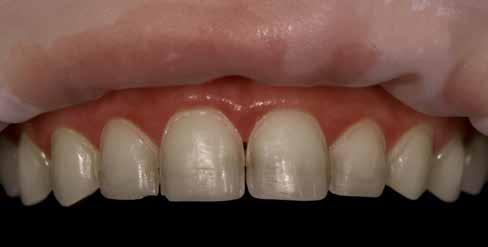

Az extrahálás és az új mosoly

A fogak extrahálása és az alveoláris plasztika teljes narkózis mellett történt meg, így teremtve ideális helyzetet a protetikai ellátáshoz. A műtéti beavatkozás után a páciens az ideglenes fogsorral távozott. Egy héttel később jött kontrollra. Nemcsak látványra változott meg nagymértékben, hanem egyértelműen magabiztosabb és önbizalommal teli volt a fellépése (12. ábra)

Összegzés

Az elsődleges terápiás szakasz kulcsfontosságú volt a teljes rehabilitáció szempontjából. A páciensnek nem csak szép, esztétikus mosolyt kölcsönzött, hanem életminőségének javulását is hozta (13. ábra). A Digital Denture folyamatnak köszönhetően a kezelés ráfordításai is alacsonyak voltak. A fiatal nő messzemenően boldog, magabiztos és motivált a következő lépéshez.